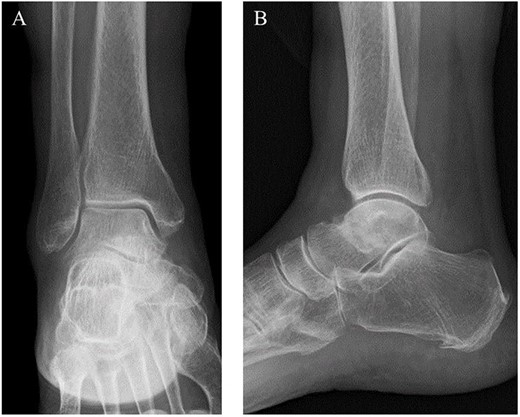

A 76-year-old female, who worked as a cleaner, complained of pain in her right ankle when going downstairs while working. She had medical history of only osteoporosis and had taking daily active vitamin D for >10 years. She was given conservative treatment for 1 month at a local clinic, however, her ankle pain persisted and so she visited our clinic. Physical examinations revealed tenderness and swelling at the anterior aspect of the ankle. Plain radiographs showed no obvious abnormal findings (Fig. 1). Magnetic resonance imaging (MRI) revealed a low signal linear line in the talar neck and a bone marrow edema around the line (Fig. 2). Non-contrast computed tomography (CT) demonstrated an obvious fracture line in the talar neck, however, the bone fragment was not displaced (Fig. 3). Based on medical histories, clinical and radiological findings, we diagnosed her with a fragility fracture of the talar neck associated with osteoporosis. Because the patient was elderly and it was difficult to treat using a prolonged non-weightbearing cast, we applied operative treatment to allow early rehabilitation. The operation was performed under spinal anesthesia in a prone position with an air tourniquet and a fluoroscopy. The posteromedial and posterolateral portals were created according to van Dijk et al. [10]. First, the posterior aspect of the talus was observed using a 4.0-mm diameter 30° arthroscope, and soft tissues around the talus (including synovium and adipose tissues) were removed with a 3.5-mm diameter motorized shaver. After confirming the posterior part of the talar body and the FHL, two 1.6-mm diameter guidewires were parallelly inserted from the posterior part of the talar body to the talar head by hindfoot endoscopy and fluoroscopy (Fig. 4A), and two cannulated 4.5-mm diameter double-threaded screws (Double Thread Screw, Meira, Nagoya, Japan) were inserted through the guidewires (Fig. 4B). The wound was sutured, and the operation was concluded (Fig. 5). Active range of motion exercises were allowed immediately after surgery, and a non-weightbearing short leg splint was worn for 1 week. Partial-weight bearing was permitted at 2 weeks and full-weight bearing was permitted at 4 weeks post-operatively. In addition, daily injections of teriparatide (Forteo, Eli Lilly and Company, Indianapolis, IN, USA) were introduced 2 weeks post-operatively. Eight weeks after the operation, the patient was able to return to work without pain or functional impairment. One year postsurgery, the patient was still working as a cleaner without any symptoms or complications.

Preoperative plain radiographs showed no obvious abnormal findings from the (A) anteroposterior and (B) lateral views.